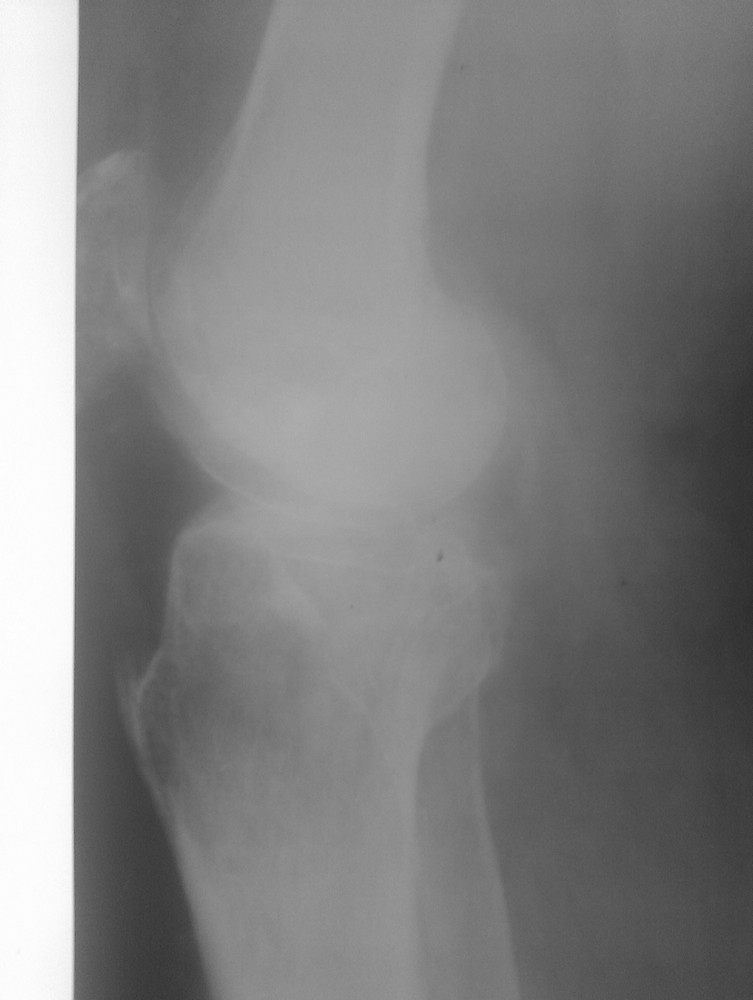

Травма от июля 2011 года, лечили консервативно гипсовым тутором (про травму лодыжек - не помнит или не знает). Через 2 недели после травмы - легочная эмболия и илеофеморальный тромбоз, находился на стац лечении. После теоретического сращения мыщелков и снятия гипсового тутора разработка движений безрезультативна, опорности конечности нет. Со слов - прыгает на костылях до самого настоящего момента.Сейчас - боль, передний ящик, люфт при нагрузке на ВБС. Боль в области внутренней лодыжки. Движения в голеностопе 5-0-15, в коленном суставе - 0-0-10, болезненные. При попытке встать полным весом и сделать шаг - нестабильность, ногу подворачивает.Ваши предложения?Пациент просит опорной ноги, сам вроде как активный (хотя толком объяснить, чем он занимался целый год, не может..)С Уважением, Останин

Неплохо было бы увидеть КТ мыщелков или рентгенограммы;) Что означает нестабильность при попытке сделать шаг? Передний ящик -сомнительно при таком объеме движений. Люфт и ногу подворачивает - а что люфтит? и куда он ее подворачивает (похоже больше чем на сгибание)? Если речь идет о вальгусном отклонении, то следует разделить: вальгус от импрессии, вальгус от боковой связочной нестабильности или повреждено и то и другое? Не совсем понятно где болевой синдром более выраженный? Если больной не может понять где болит больше - я бы шел от переферии к центру (плюс к тому, на моем нечетком мониторе голеностоп выглядит хуже).